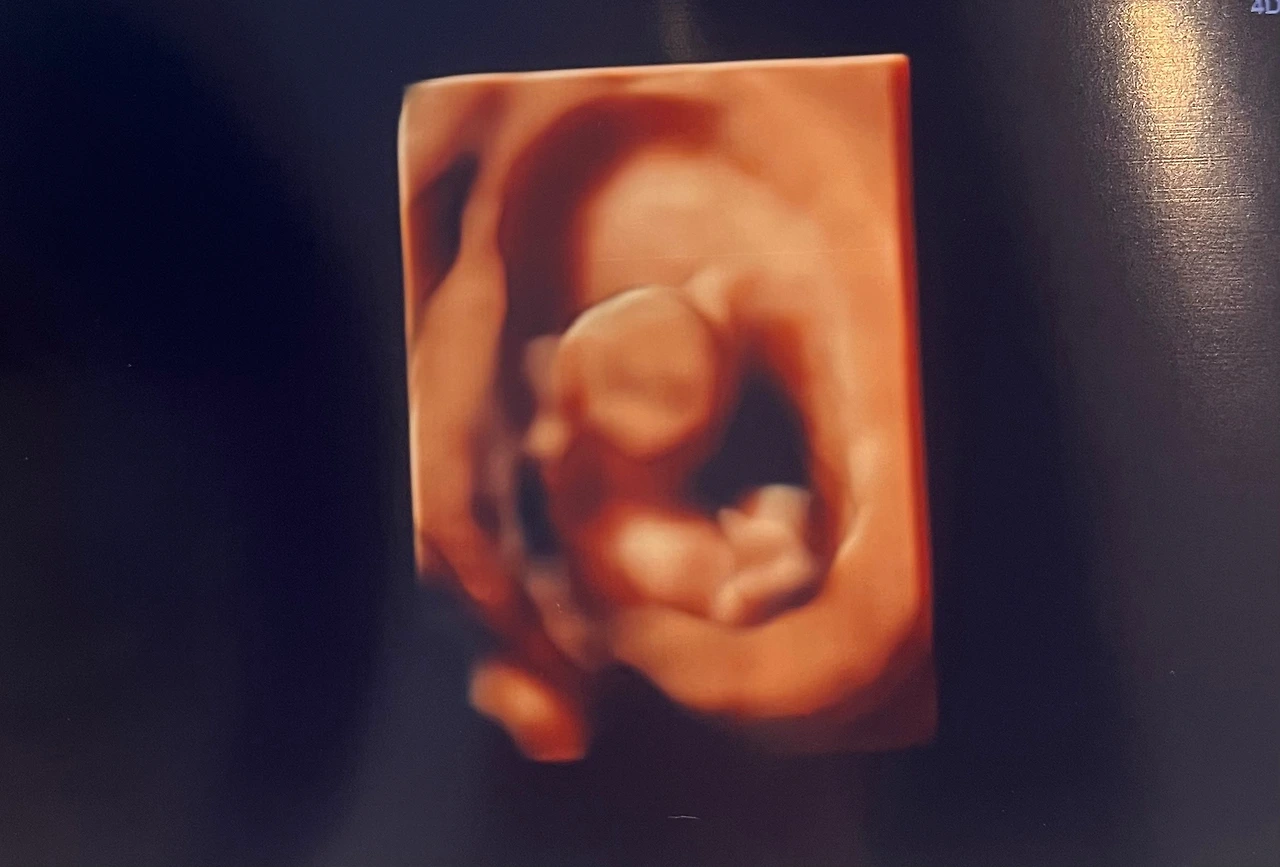

검사는 생각보다 간단했다. 산모의 채혈을 뽑는 것과 초음파를 보는 것 두 가지뿐이었다. 피검사 결과는 다음 정기검사에 같이 이야기를 해준다고 했고, 초음파는 평소 의사 선생님 진료실에서 보던 것과는 달리 정밀초음파실에서 입체초음파로 자세히 봤다. 평소보다 오래 봤는데, 이 시기에 의료진이 확인해야 하는 부분이 있는 것 같다. 목투명대, 코뼈, 몸길이, 양팔, 양다리, 손가락, 발가락 등 외형적으로 봤을 때 이상이 없는지를 봤다. 이때 화면 속으로 너무 귀여운 아이에게 감동받으면서도 동시에 의료진의 입에서 예상치 못한 말이 나오진 않을까 하는 걱정이 동시에 들었다.

엄마는 벌써 코가 너무 오뚝하지 않냐고 설레발을 떨고 있어서 정말 곤란해..

초음파실에서 너무 활발하게 움직여서 사진 찍는데 애먹었단다.

그래도 잘 노는 모습을 보니까 너무 행복하다. 엄마를 쏙 빼닮은 것 같아.

'만세!'하고 있는 모습에 검사하면서 다 같이 빵 터졌어.